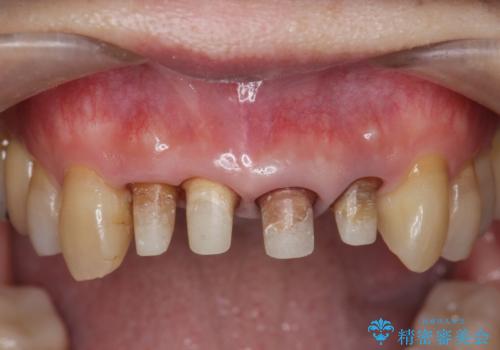

不十分な根管治療を含めたセラミッククラウンのやりかえ治療を計画します。

- 52万円(仮歯・ファイバーコア・ジルコニアクラウン×4)費用は治療当時の料金となります

クラウン治療は経年的に歯ぐきの位置が変わり汚れが溜まってしまったり、見た目が悪くなるなどの問題が出てくることがあります。